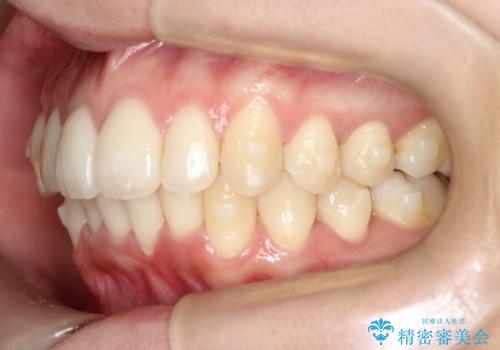

- 前歯のでこぼこが気になると来院されました。

奥歯の噛み合わせは綺麗に噛んでいたため、前歯の叢生(でこぼこ)を、短期間で治療完了するように計画しました。

奥歯の噛み合わせは整っていたため、前歯の並びを美しく修正することに専念できました。マウスピース矯正による治療で短期間で改善しました。